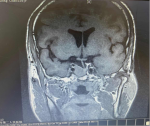

湘乡市二医院确诊罕见垂体TSH瘤